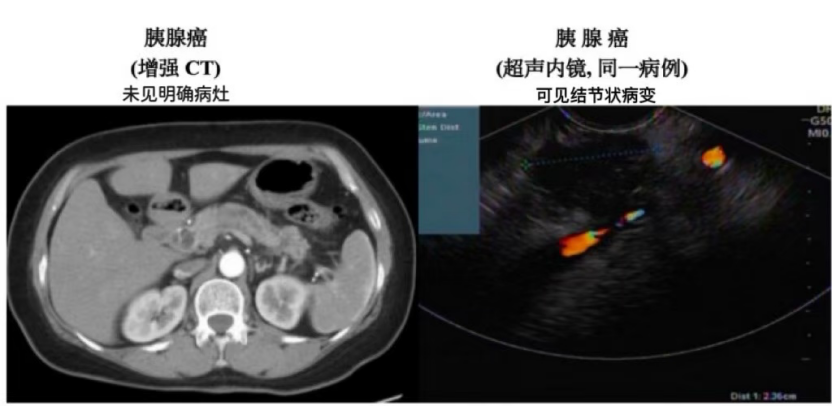

胆胰器官被肠道、血管等复杂结构包裹,传统CT、MRI 等影像学检查,对微小早期病变的识别能力有限。而超声内镜将内镜与超声融合,经内镜通道送入超声探头至消化道,可近距离扫描胆胰,获取高分辨率图像,精准捕捉细微异常,是当前检出率最多的手段。

谈及超声内镜优势,相马宁教授举例说明:胰腺癌早期筛查中,它能捕捉胰腺实质内微小占位,发现直径不足1厘米的肿瘤;面对胆管疾病,可准观察胆囊及胆管、管腔结石、狭窄及肿瘤侵犯情况,大幅提升诊断准确性。